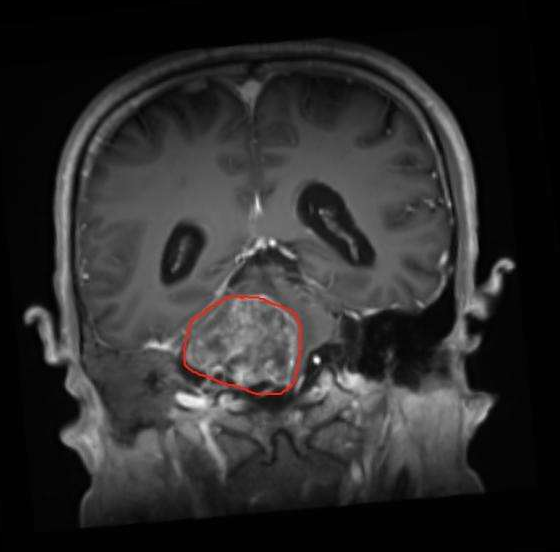

橋腦延髓腦干膠質(zhì)瘤能活多久?腦干膠質(zhì)瘤性質(zhì)幾乎皆為膠質(zhì)瘤,以星形細(xì)胞瘤和多形膠質(zhì)瘤母細(xì)胞瘤較為常見,部分可為神經(jīng)節(jié)膠質(zhì)瘤和室管膜瘤,位于腦干上段,主要是低度惡性的...

腦干膠質(zhì)瘤能活多久?膠質(zhì)瘤的治療一般提倡綜合治療,即手術(shù)切除+化療+放療,目的是,延緩復(fù)發(fā)。但由于腦干長膠質(zhì)瘤手術(shù)難度大,易復(fù)發(fā),常采用放射治療。目前,采用...

從現(xiàn)有的記錄來看,術(shù)后膠質(zhì)瘤患者生存期較長已經(jīng)可達(dá)10年以上,如果是低級別膠質(zhì)瘤中位生存期一般在8年到10年之間,文獻(xiàn)報道有偏良性的膠質(zhì)瘤患者經(jīng)過治療存活26年的,三級以上...

診斷為腦干神經(jīng)膠質(zhì)瘤后,您可能想知道您的治療選擇,神經(jīng)膠質(zhì)瘤的發(fā)展方式以及成年腦干神經(jīng)膠質(zhì)瘤患者的前景如何。雖然您的醫(yī)生是解決您個人預(yù)后的更佳人選,但以下信息將使...